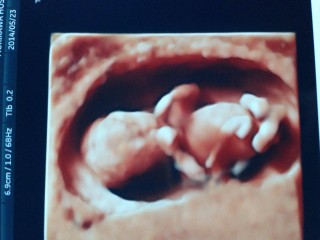

妊娠12目の時のエコーです。 とても元気で驚きました。まるで魚が川の上を飛び跳ねるように激しく動いていて、こんなに小さいのに強いエネルギーを感じました。 かと思えば、疲れてしまったのか、まったく動かずじーっとしたり。とにかく初めてのエコーだったのでとても感動しました。

元気良く動いていました!

頭からおしりまで約6cm♪ 寝てると思ったら起きたのか手足をバタバタさせて元気な姿が見られて安心しました(*^^*) 指が可愛いくて癒されてます♪

ちゃんと人間の形になっててビックリ!

可愛いあんよが見えました★

身長は6cmです^ ^

元気がよくパタパタと元気にうごいていました。